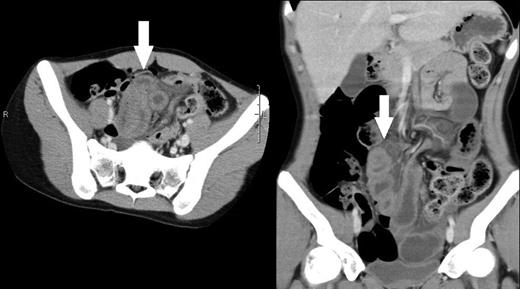

Abdominal computed tomography (CT) revealed loops of edematous small intestines which possible gangrenous changes (Fig.1).

Computed tomographic scans of axial and coronal views of abdomen demonstrating edematous small intestines (arrows).